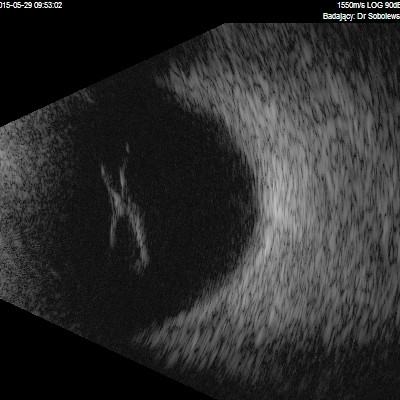

Dziwne mętów

Przedstawiane obrazy ultrasonograficzne® są oryginalne i pochodzą z mojej praktyki lekarskiej